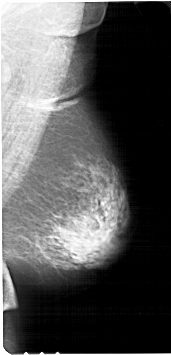

A_1123_1.RIGHT_MLO

RIGHT_MLO LINES 6736 PIXELS_PER_LINE 3241 BITS_PER_PIXEL 12 RESOLUTION 43.5 NON_OVERLAY